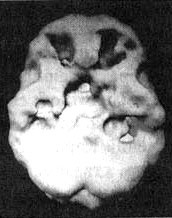

Мозг Роба. Алкогольная, кокаиновая и метамфетаминовая зависимость

Иллюстрация к книге — Измените свой мозг - изменится и жизнь! [i_090.jpg]

Трехмерное изображение поверхности, вид сверху. Обратите внимание на многочисленные «провалы» активности и сморщенный вид мозга в то время, когда Роб злоупотреблял этими веществами.